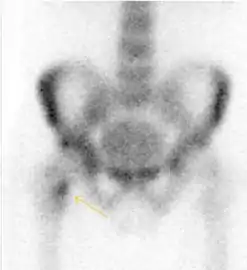

In this case, Tc 99 scintigraphy shows a band of uptake[1]

Bone scanning in people with hip pain can be complementary to other imaging studies, mainly in indeterminate bone lesions to clarify whether it is an active lesion with abnormal radiotracer accumulation. Nevertheless, MRI has replaced scintigraphy in the diagnosis of most of these conditions. An example is stress or insufficiency fractures: increased uptake is usually present in around 80% of fractures within 24 h, and 95% of fractures reveal activity by 72 h following trauma, showing an overall sensitivity of 93% and specificity of 95%. MRI is superior to bone scans in terms of sensitivity (99%-100%) and specificity (100%). Moreover, a bone scan does not provide detailed anatomical location of the fracture, and further imaging is usually required.[1]